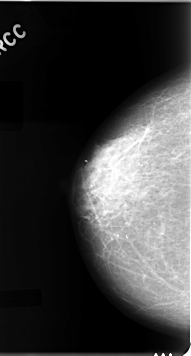

C_0050_1.RIGHT_CC

RIGHT_CC LINES 4616 PIXELS_PER_LINE 2480 BITS_PER_PIXEL 12 RESOLUTION 50 NON_OVERLAY

RIGHT_MLO LINES 4664 PIXELS_PER_LINE 2584 BITS_PER_PIXEL 12 RESOLUTION 50 NON_OVERLAY